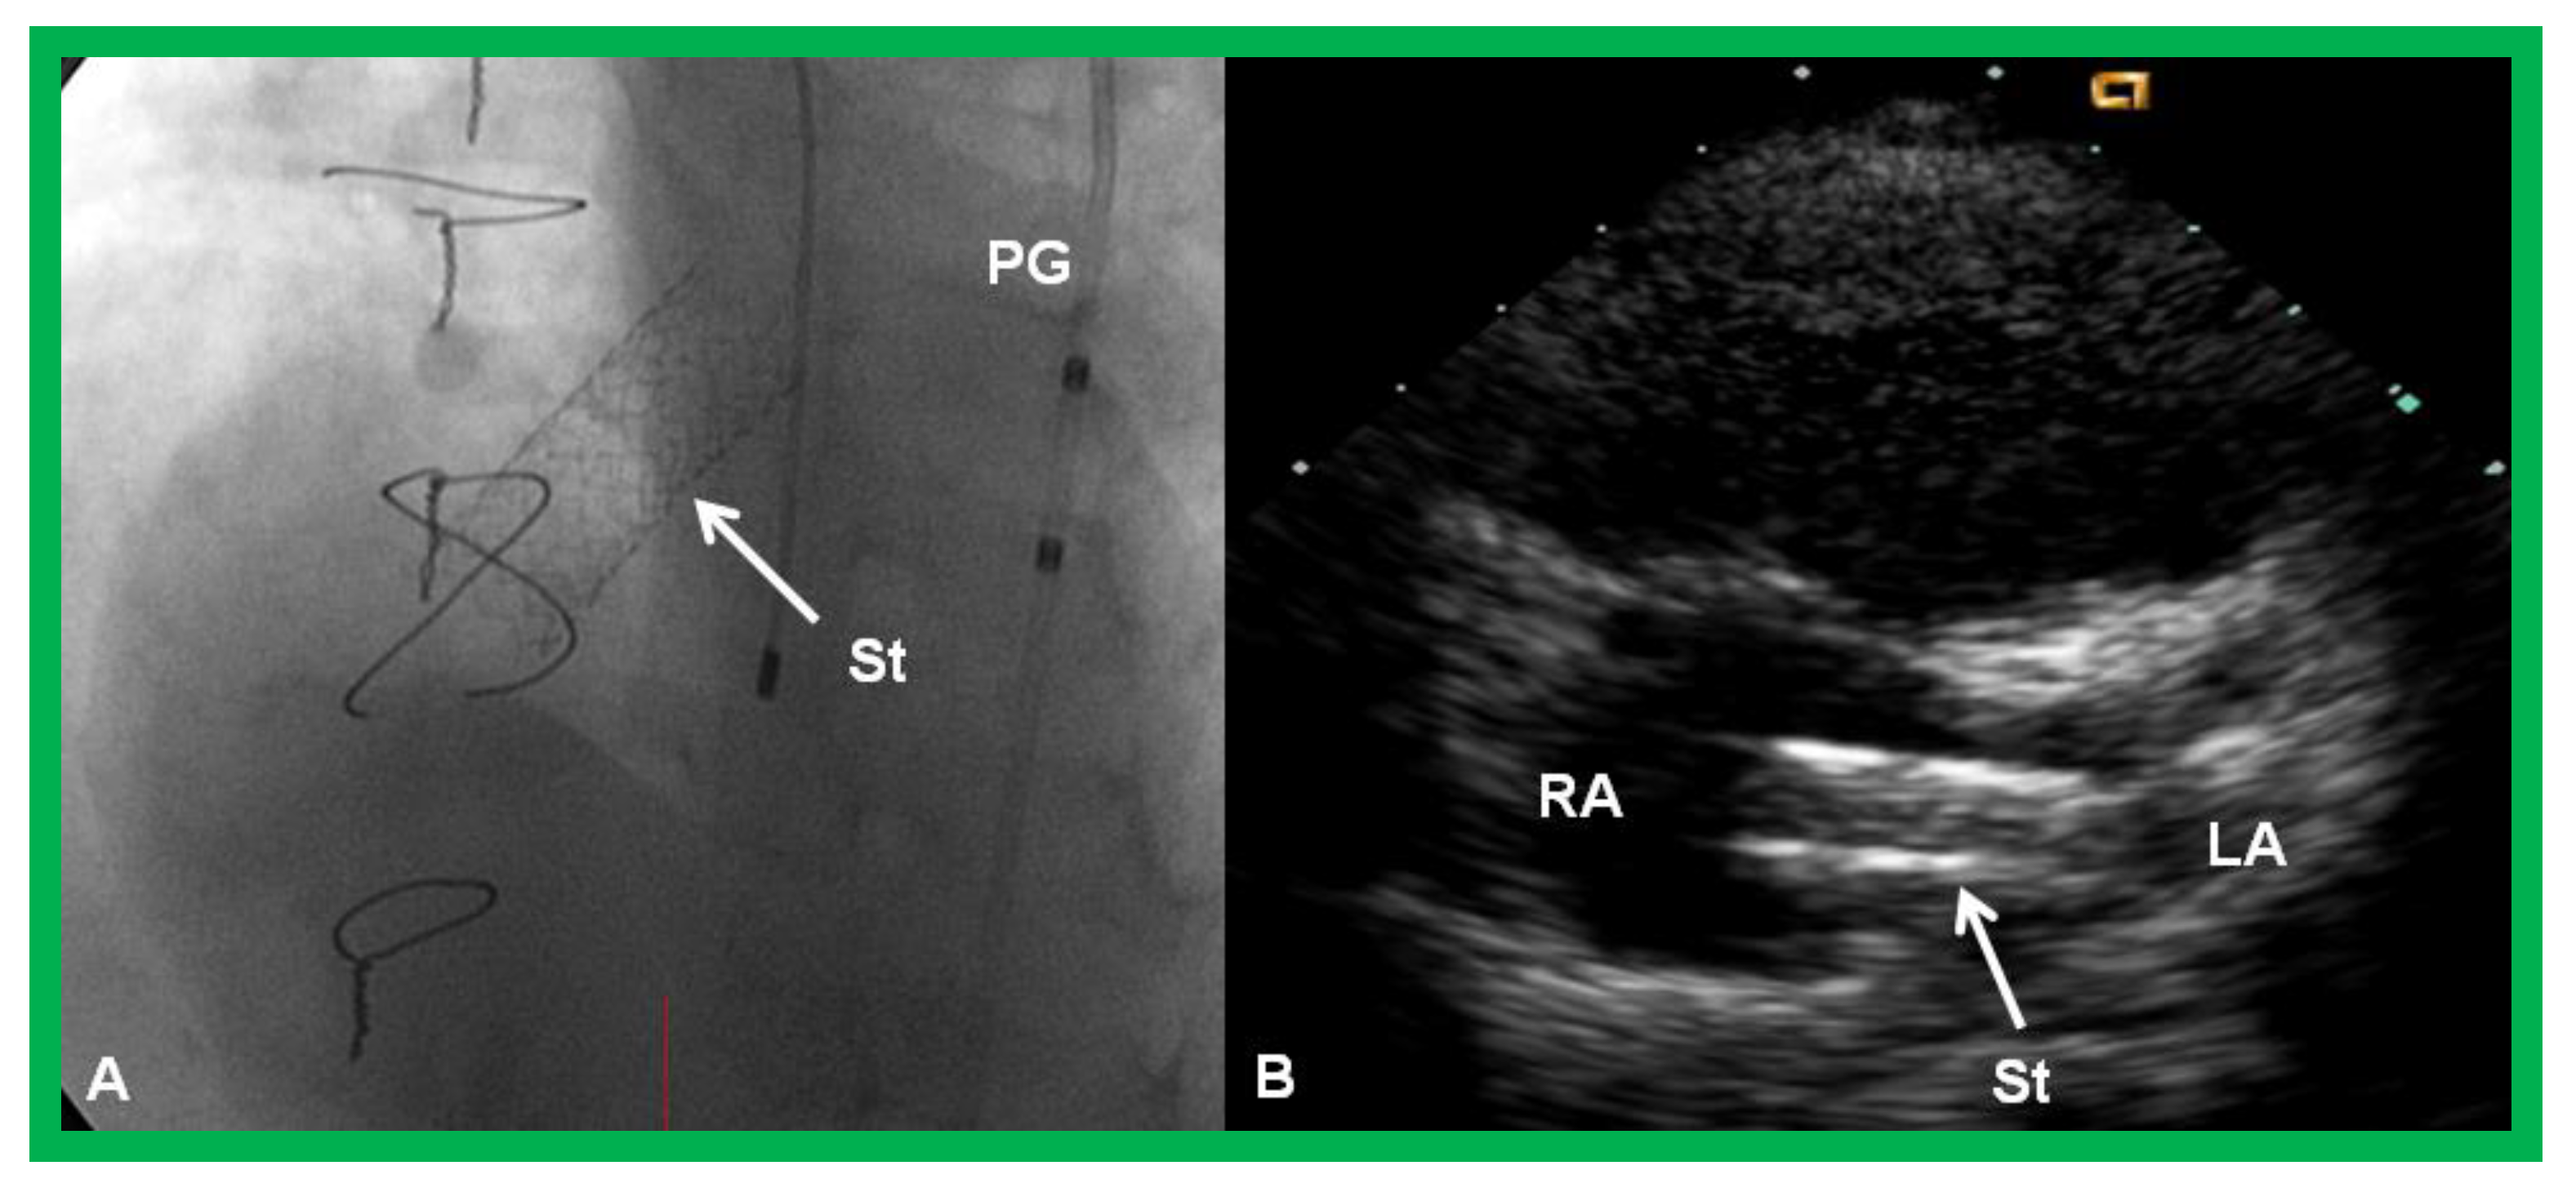

- Gewillig, D.; Boshoff, L.; Mertens, L. Creation with a stent of an unrestrictive lasting atrial communication. Cardiol. Young 2002, 12, 404–407. [Google Scholar] [CrossRef] [PubMed]

- Eicken, A.; Gildein, H.P.; Schreiber, C.; Balling, G.; Hess, J. Stenting of a restrictive foramen ovale in a patient with hypoplastic left heart syndrome. Intern. J. Cardiol. 2006, 113, 254–256. [Google Scholar] [CrossRef] [PubMed]

- Rao, P.S. Neonatal Catheter Interventions. In Cardiac Catheterization and Imaging (From Pediatrics to Geriatrics); Vijayalakshmi, I.B., Ed.; Jaypee Publications: New Delhi, India, 2015; pp. 388–432. [Google Scholar]

- Atz, A.M.; Feinstein, J.A.; Jonas, R.A.; Perry, S.B.; Wessel, D.L. Preoperative management of pulmonary venous hypertension in hypoplastic left heart syndrome with restrictive atrial septal defect. Am. J. Cardiol. 1999, 83, 1224–1228. [Google Scholar] [CrossRef]

- Justino, H.; Benson, L.N.; Nykanen, D.G. Transcatheter creation of an atrial septal defect using radiofrequency perforation. Catheter. Cardiovasc. Interv. 2001, 54, 83–87. [Google Scholar] [CrossRef]